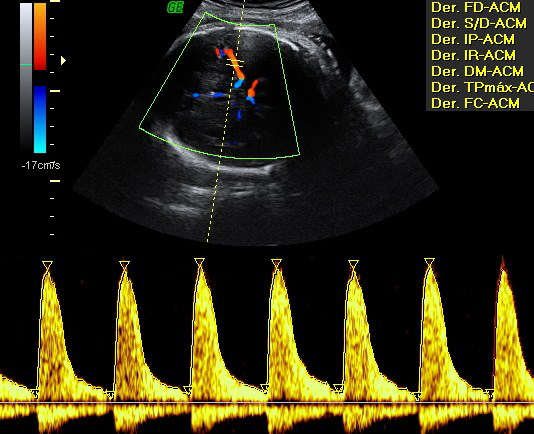

Se realiza una nueva evaluación de la circulación cerebral y umbilical.